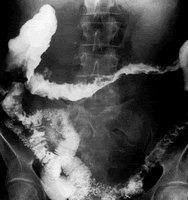

共7项有关活动期溃疡性结肠炎的随机对照试验符合纳入标准。结果显示,传统疗法[皮质类固醇激素和(或)免疫抑制剂]效果不佳的中度至重度溃疡性结肠炎患者,TNF-α阻滞剂英夫利昔单抗(于0、2和6周进行3次静脉输注)可使患者8周时的临床缓解率、内镜下黏膜愈合率和临床有效率分别增加2.22倍、88%和99%;单次应用英夫利昔单抗也可使治疗后90天内需行结肠切除术的患者比例降低56%。

评价者结论:经皮质类固醇激素和(或)免疫抑制剂治疗效果不佳的中度至重度溃疡性结肠炎患者,英夫利昔单抗治疗可有效诱导临床缓解,促进黏膜愈合,并至少降低短期内行结肠切除术的危险。但临床医师也应注意此药的潜在副作用,如过敏反应和感染等。, 百拇医药